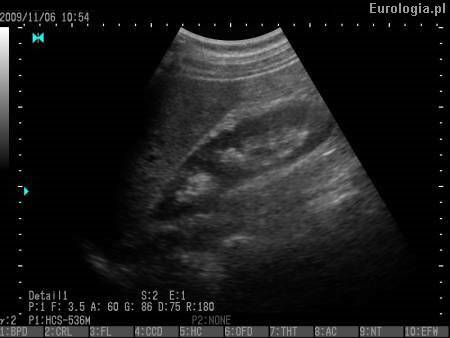

Video: Obraz USG układu moczowego.